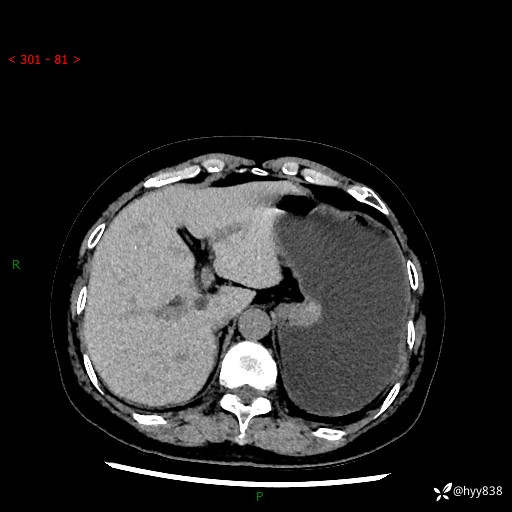

胃CT平扫+增强(动脉期+静脉期)

三期CT值:46hu 58hu 75hu